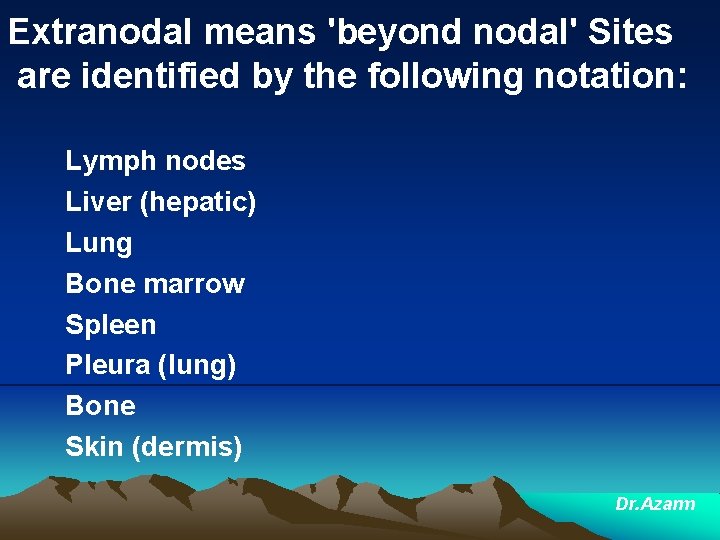

Extranodal means 'beyond nodal' Sites are identified by the following notation: Lymph nodes Liver (hepatic) Lung Bone marrow Spleen Pleura (lung) Bone Skin (dermis) Dr. Azarm